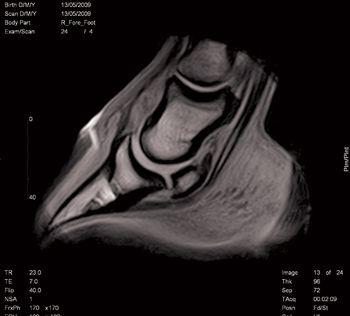

A look at the pros and cons of standing vs. recumbent magnetic resonance imaging systems.